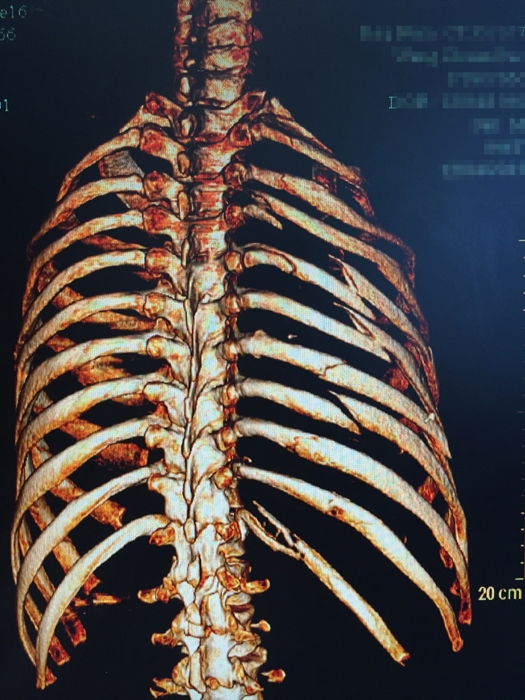

??? 說起張成的經(jīng)歷,讓人唏噓不已。2015年12月4日,46歲的張成不慎從四層高樓墜落,當(dāng)場不省人事。家人立即將張成送入當(dāng)?shù)蒯t(yī)院搶救,經(jīng)檢查發(fā)現(xiàn)張成血氣胸,創(chuàng)傷性濕肺,全身多處骨折,光肋骨就有11根骨折,右側(cè)股骨骨折,右側(cè)肱骨下段粉碎性骨折,最嚴重的是還有脾破裂,骨盆骨折和胸椎骨折。因傷勢嚴重,當(dāng)?shù)蒯t(yī)院建議家屬將張成轉(zhuǎn)到上一級醫(yī)院。

患者入院時的X影像